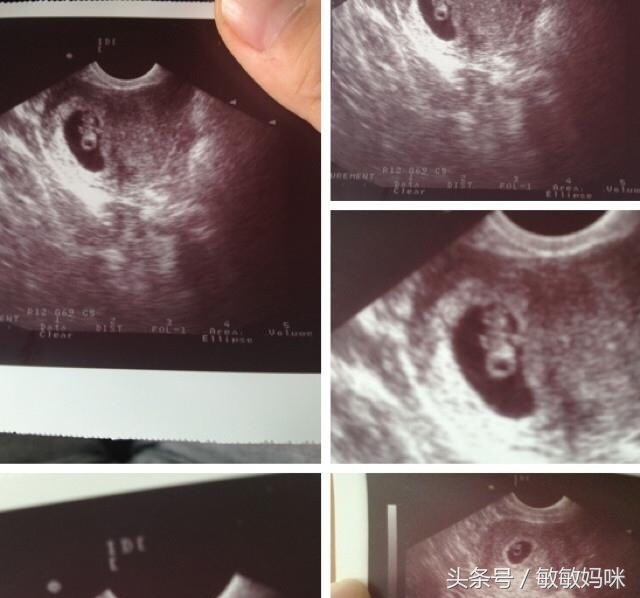

小婕夫妻俩都不是迷信的人,所以刚怀孕,身边的亲戚好友都知道,得到大家的祝福,小宝宝也健健康康!转眼就12周了,肚子一天一天的大!小婕谈起宝宝更是一脸幸福,真是羡慕不已啊!

怀孕就这么简单,宝宝健健康康的到来!